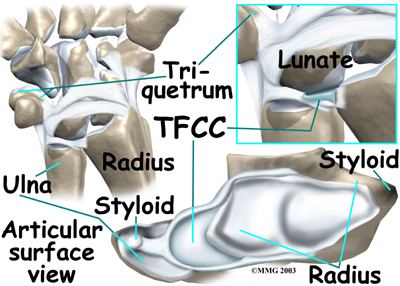

At the wrist, the end of the ulna bone of the forearm articulates with two carpal bones, the lunate and the triquetrum.

At the wrist, the end of the ulna bone of the forearm articulates with two carpal bones, the lunate and the triquetrum.

A unique structure mentioned earlier, the (TFCC), sits between the ulna and these two carpal bones.

The TFCC is a small cartilage pad that cushions this part of the wrist joint. It also improves the range of motion and gliding action within the wrist joint.